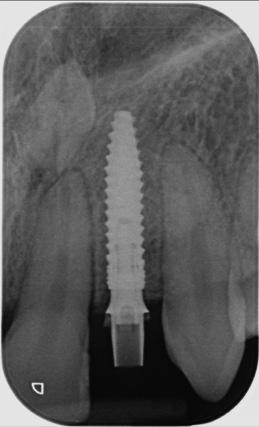

CASE STUDY

Guided implant approach for reproducible results, page 28